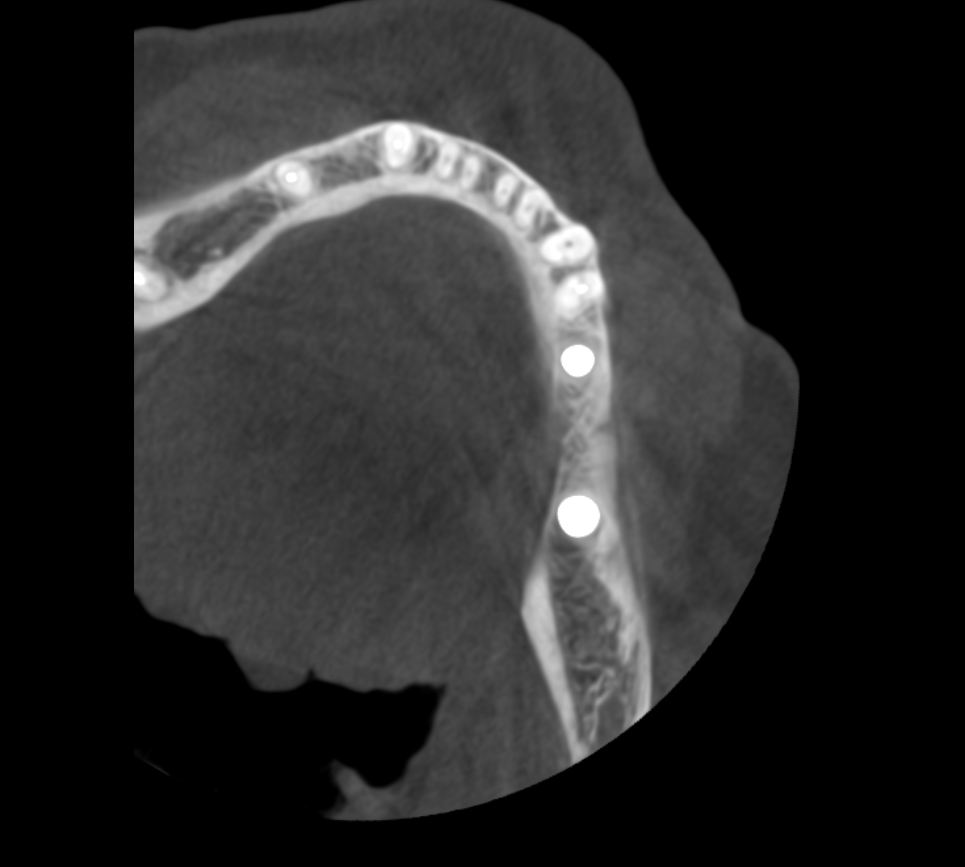

Простой. Надежный. Дешевый. Способ остеопластики.